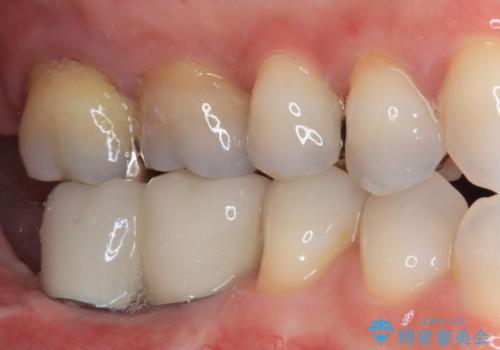

欠損と治療途中の奥歯 インプラント治療と補綴治療